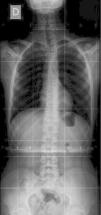

Presentamos un caso clínico de osteoma osteoide como causa de escoliosis cervicodorsal dolorosa.

We report the case of an adolescent with an osteoid osteoma causing painful, cervical scoliosis.